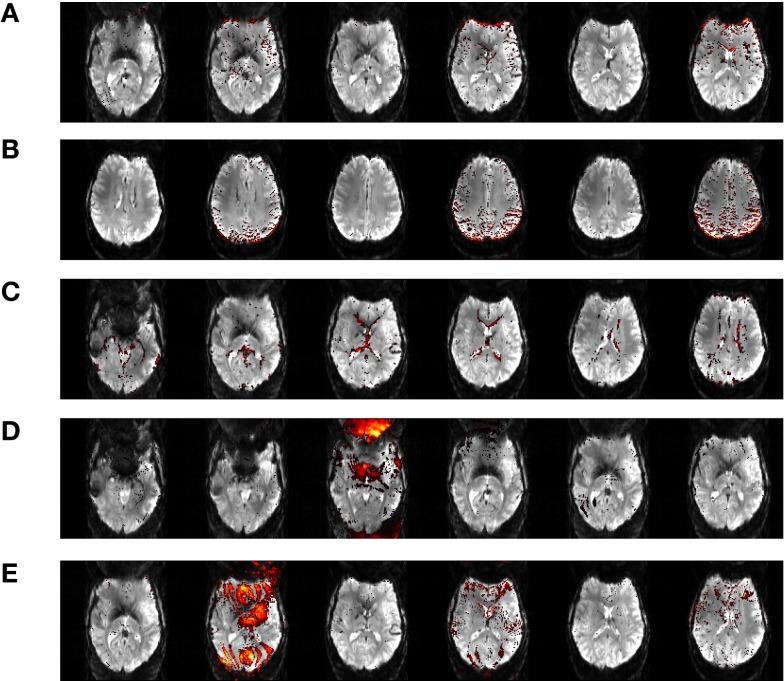

Increased BOLD sensitivity at 7 T offers the possibility to increase the reliability of fMRI, but ultra-high field is also associated with an increase in artifacts related to head motion, Nyquist ghosting, and parallel imaging reconstruction errors. In this study, the ability of independent component analysis (ICA) to separate activation from these artifacts was assessed in a 7 T study of neurological patients performing chin and hand motor tasks. ICA was able to isolate primary motor activation with negligible contamination by motion effects. The results of General Linear Model (GLM) analysis of these data were, in contrast, heavily contaminated by motion. Secondary motor areas, basal ganglia, and thalamus involvement were apparent in ICA results, but there was low capability to isolate activation in the same brain regions in the GLM analysis, indicating that ICA was more sensitive as well as more specific. A method was developed to simplify the assessment of the large number of independent components. Task-related activation components could be automatically identified via these intuitive and effective features. These findings demonstrate that ICA is a practical and sensitive analysis approach in high field fMRI studies, particularly where motion is evoked. Promising applications of ICA in clinical fMRI include presurgical planning and the study of pathologies affecting subcortical brain areas.

在 7T 下增加 BOLD 敏感度可以提高 fMRI 的可靠性,但超高场也与与头部运动、奈奎斯特鬼影和并行成像重建错误相关的伪影增加有关。在这项对进行下巴和手部运动任务的神经科患者的 7T 研究中,评估了独立成分分析(ICA)将激活与这些伪影分离的能力。ICA 能够隔离主要运动激活,而运动影响的污染可忽略不计。相比之下,这些数据的广义线性模型(GLM)分析结果受到运动的严重污染。ICA 结果显示出次级运动区、基底节和丘脑的参与,但在 GLM 分析中分离相同脑区的激活能力较低,这表明 ICA 更敏感也更特异。开发了一种方法来简化对大量独立成分的评估。通过这些直观有效的特征,可以自动识别与任务相关的激活成分。这些发现表明,ICA 是高磁场 fMRI 研究中一种实用且敏感的分析方法,特别是在诱发运动的情况下。ICA 在临床 fMRI 中的有前景的应用包括术前规划和研究影响皮质下脑区的病理学。